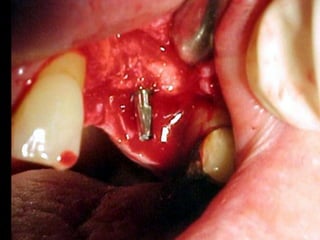

NO

Area crítica inmediata para el

implante

Unión gingivo-implantaria

Inicio de la periimplantitis

La principal causa de fracaso de los implantes dentales es la

isquemia ósea periimplantaria.